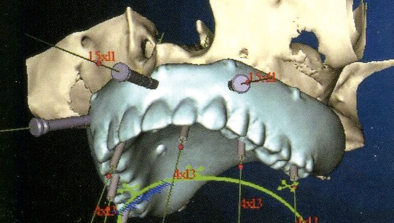

最低4本のインプラントを埋入し、それらを連結し、半日で固定式の仮歯まで入れて審美性、機能性を一日でとりもどせる革新的な治療。

1.従来インプラントは歯茎の中の骨に結合する3〜6ヶ月までは、歯をいれて噛ませることはできないと言われてきましたが、特殊な手術法によりインプラントを埋入し、4本〜6本を連結固定することにより、手術したその日からインプラントで食事を噛んでもらうことができるようになります。